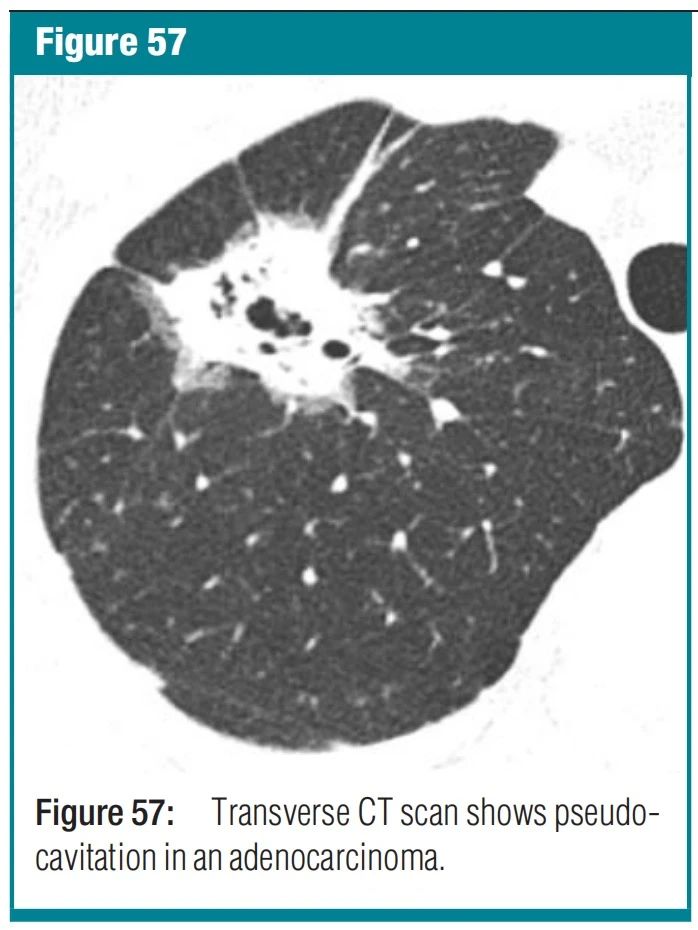

图5 pseudocavity-假空洞 CT 扫描-假空洞表现为肺结节、肿块或实变区域中的椭圆形或圆形低衰减区域,代表幸存的实质、正常或扩张的支气管或局灶性肺气肿,而不是空洞。这些假空洞的直径通常小于 1 厘米。它们已在腺癌、细支气管肺泡癌和传染性肺炎等良性疾病患者中得到描述。